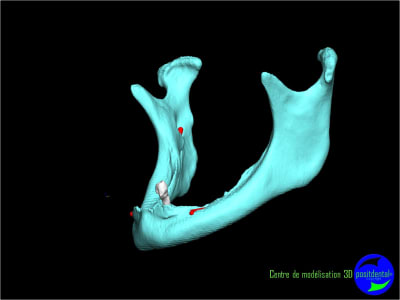

Résorbée genre comme ça?